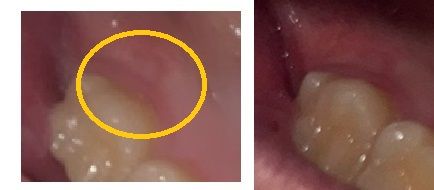

오른쪽 위 마지막 어금니에요

저렇게 잇몸이 들어가 있는데 이유를 모르겠어요

통증은 없고 고름 찬 것처럼 튀어나온것도 없어요

만지면 옆이랑 느낌이 좀 다르긴 해요

사진으로 보기에는 사랑니 전후에도 있었고 해당 부위의 범위가 변한다거나 염증소견이 보이지는 않아서 너무 걱정하지 않으셔도 되겠습니다. 통증도 없다고 하시니 그냥 정상적인 조직으로 보입니다.